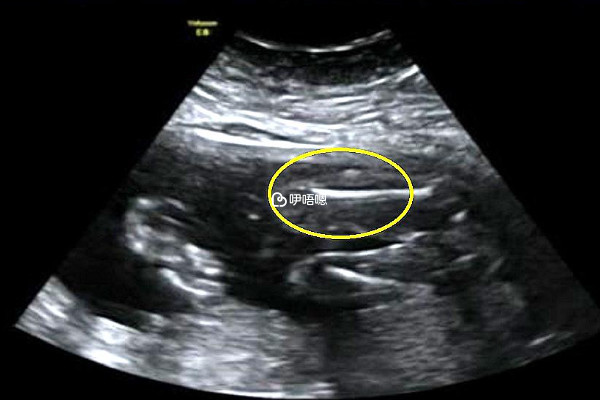

孕8周時女性內分泌失調並且孕酮低是會導致胎停的,無論是胚胎著床還是胚胎繼續發育,都需要依靠人體的內分泌激素進行調節,胎兒才能汲取營養來生長髮育,如果此時女性內分泌失調孕酮值低,那胎兒生長髮育也會受阻,嚴重時就會直接停止發育。建議此時女性應該在醫生指導下使用黃體支援藥物來調整體內激素平衡。

女性孕8周時,除了內分泌失調,還有很多的因素都會導致胚胎停育。例如胎盤早剝、臍帶脫垂、臍帶繞頸纏體、臍帶打結等,可引起胎兒發生缺氧,在子宮內死亡。還有胎兒自身染色體異常、胎兒生長髮育受限、胎兒宮內感染、胎兒嚴重畸形、嚴重遺傳性疾病等胎兒自身存在疾病,使其不能正常發育成足月兒,也可以引起胎兒在妊娠期內死亡。